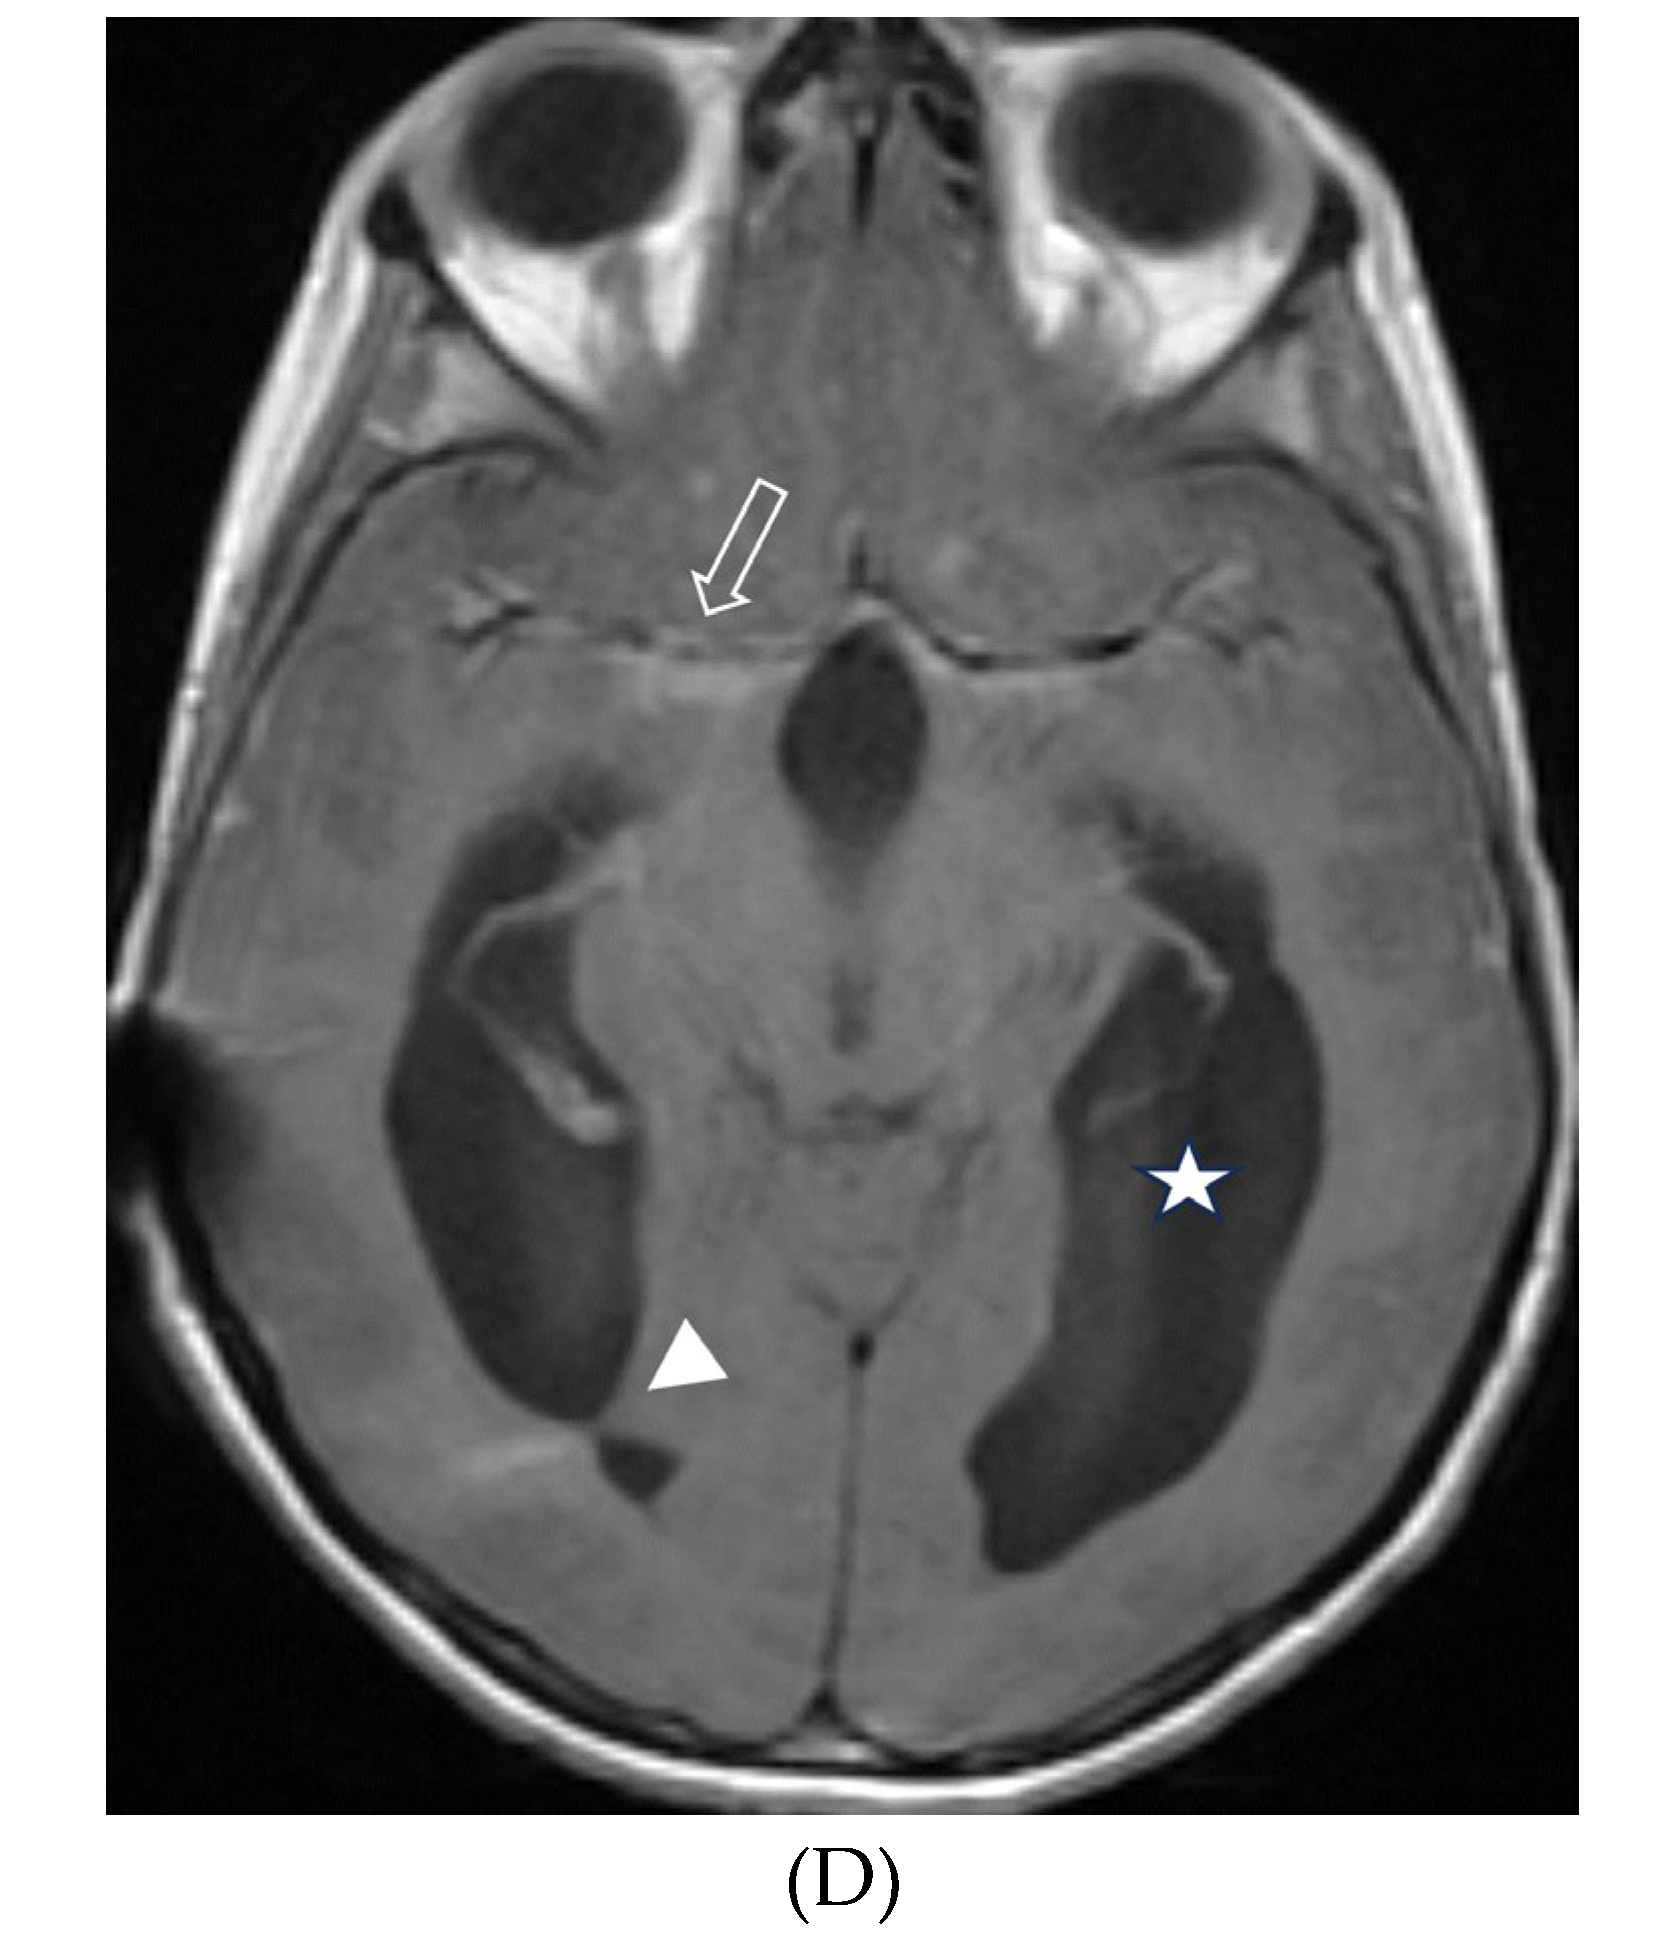

- Gabbay LB, Leite Cda C, Andriola RS, Pinho Pda C, Lucato LT. Histiocytosis: a review focusing on neuroimaging findings. Arq Neuropsiquiatr. 2014 Jul;72(7):548-58. PMID: 25054989. [CrossRef]

- Ribeiro BNF, Muniz BC, Marchiori E. Langerhans cell histiocytosis with isolated meningeal involvement: findings on magnetic resonance imaging. Radiol Bras. 2018 Sep-Oct;51(5):343-344. PMID: 30369670; PMCID: PMC6198827. [CrossRef]

- Prayer D, Grois N, Prosch H, Gadner H, Barkovich AJ. MR imaging presentation of intracranial disease associated with Langerhans cell histiocytosis. AJNR Am J Neuroradiol. 2004 May;25(5):880-91. PMID: 15140741; PMCID: PMC7974468.

- Martin-Duverneuil N, Idbaih A, Hoang-Xuan K, Donadieu J, Genereau T, Guillevin R, Chiras J; French Langerhans Cell Histiocytosis Study Group. MRI features of neurodegenerative Langerhans cell histiocytosis. Eur Radiol. 2006 Sep;16(9):2074-82. Epub 2006 Apr 20. PMID: 16625352. [CrossRef]